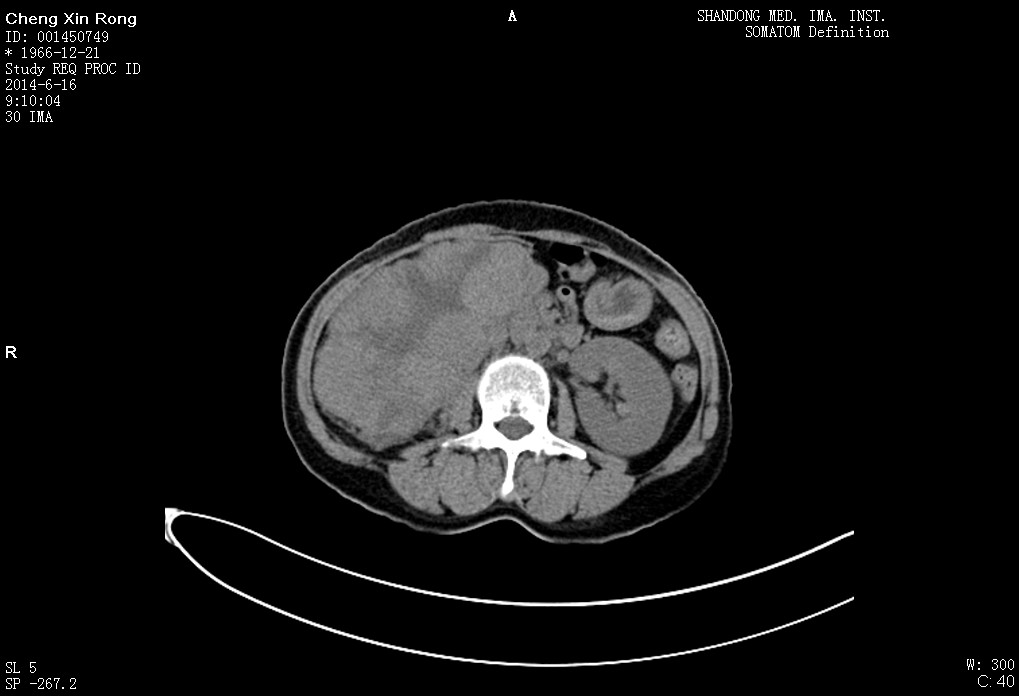

该患者4个月前无明显诱因开始出现发热并右侧腰痛,就诊于当地医院,该医院行MRI检查后认为瘤体巨大,手术风险极高,遂建议其求诊上级医院。我院泌尿外科毕东滨副主任医师接诊该患者后以“右肾占位”收住院。患者入院后行CT检查提示:右肾巨大包块,与下腔静脉关系密切,将下腔静脉推挤向左方。肾静脉被压迫明显,管径被挤压,肿瘤上极与肝脏关系不明。全科组织病案讨论,集思广益,对于手术慎之又慎,反复研究病情,各科室密切协同,精心进行术前准备,并与患者充分沟通交代病情及明确手术方案及风险。在院内肝胆外科、麻醉科、血管外科等专家积极参与下,最终确定了治疗方案。毕东滨主任在术前指出:虽然手术风险大,手术难度高,但是作为一名省医人,要排除万难,发扬革命的救死扶伤精神,尽全力进行救治。

手术于2014-06-19在气管插管全麻下进行,由毕东滨副主任医师主刀,经过7个小时的紧张手术,将患者右侧肾上腺与右肾一并完整切除送检,瘤体称重约1.7Kg,约24X15cm大小,术中切除肾蒂周围淋巴结3枚,一并送检。